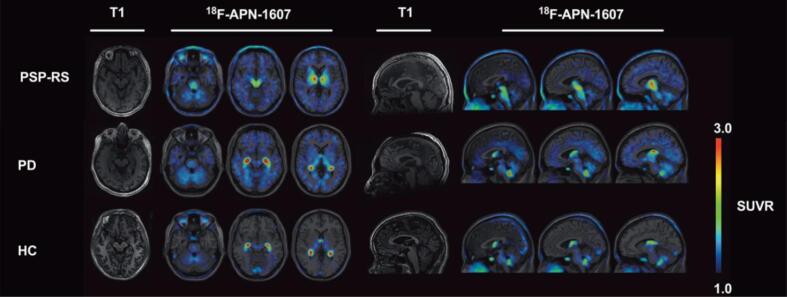

Additional evidence for [18F]PM-PBB3′s utility in imaging 4R tau has been uncovered over the past year ref. [72], ref. [73], ref. [74], ref. [75]. One study reports that increased tau accumulation over time corresponds with significant [18F]PM-PBB3 uptake in patients with MAPT mutations ref. [72]. Overall, the researchers conclude that [18F]PM-PBB3 is more effective than first-generation tracers in binding to 4R tau and tracking the accumulation of this isoform over time in MAPT mutation carriers. Lending similar support, the first antemortem study using [18F]PM-PBB3 in PSP patients displays that tracer retention is heightened in the midbrain, subthalamic nucleus, and cerebellar dentate nucleus of these patients ref. [73]. In addition to these regions, Li et al ref. [74] report increased tracer binding in the striatum, putamen, globus pallidus, thalamus, tegmentum, substantia nigra, pontine base, red nucleus, raphe nuclei, and locus coeruleus (Fig. 4). Furthermore, clinical severity of PSP is indicated by the magnitude of tracer binding in the subthalamic nucleus, midbrain, substantia nigra, red nucleus, pontine base, and raphe nucleus ref. [74]. Similar success was observed in the only study using this tracer in CBD: researchers find that [18F]PM-PBB3 accumulation is pronounced in the occipital cortex, basal ganglia, thalamus, midbrain, subcortical region, and asymmetrical neocortex of CBD patients ref. [75].